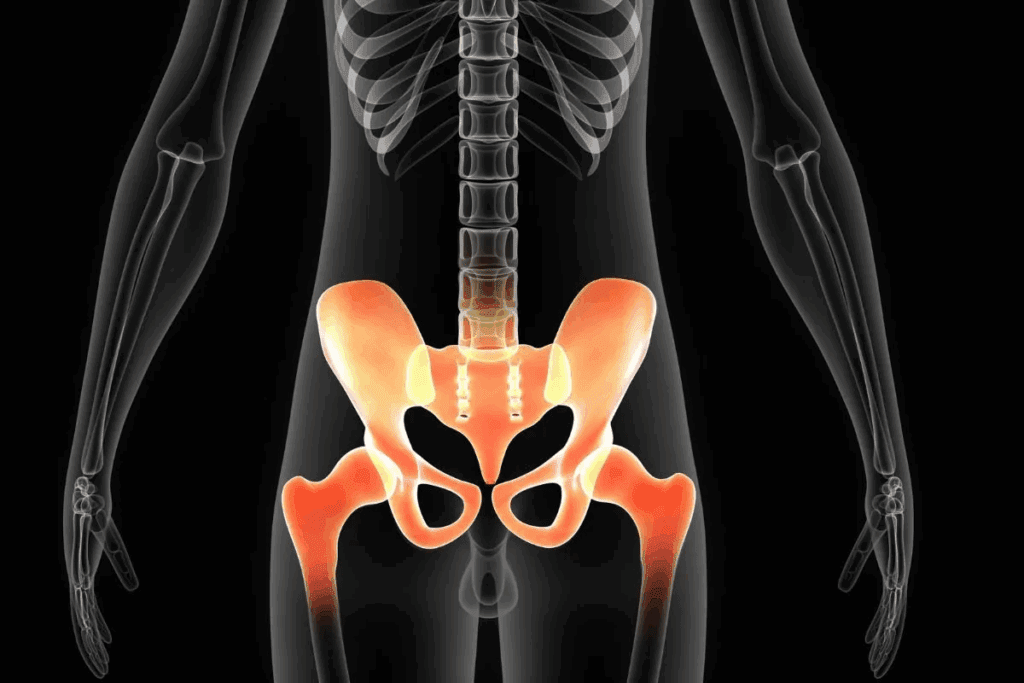

Our team prioritizes patients with connective tissue disorders like Ehlers-Danlos syndrome. These conditions reduce the joint’s natural resistance to traumatic forces. Prior ankle injuries also leave residual instability – 68% of recurrent cases involve individuals with untreated sprains.

Weak ligaments from prior sprains, congenital joint abnormalities, or conditions like Ehlers-Danlos syndrome reduce natural stability. Athletes in sports requiring rapid pivoting also face higher risks due to repetitive stress on the ankle’s support structures.